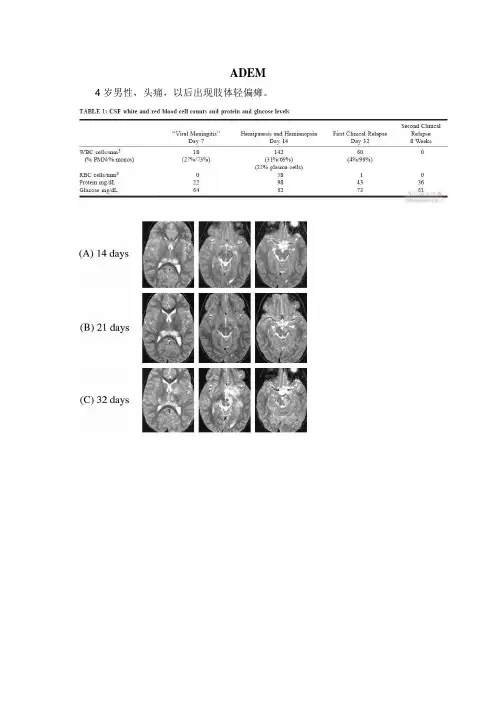

ADEM 4岁男性,头痛,以后出现肢体轻偏瘫。